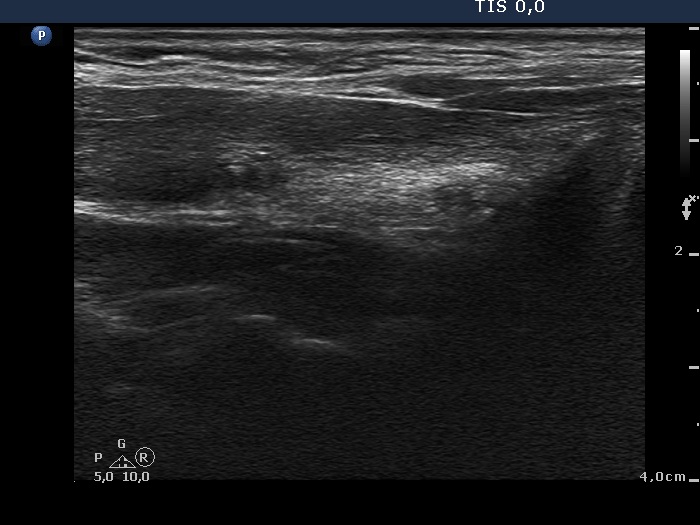

First examination - before surgery (first and second rows of images)

Ultrasonography. The right lobe was echonormal. There was a moderately hypoechogenic, inhomogeneous nodule with blurred borders in the left side of the isthmus. Another cystic nodule was present in the left thyroid.

Cytology of the solid nodule resulted in papillary cancer.

Total thyroidectomy was performed. Histopathology disclosed papillary cancer based on the nodule aspirated and hyperplastic nodule based on the nodule in the left lobe. The tumor reached the capsule of the thyroid and the maximal diameter of the carcinoma was 8 mm. The tumor cells displayed significant atypia and even pleomorphism.